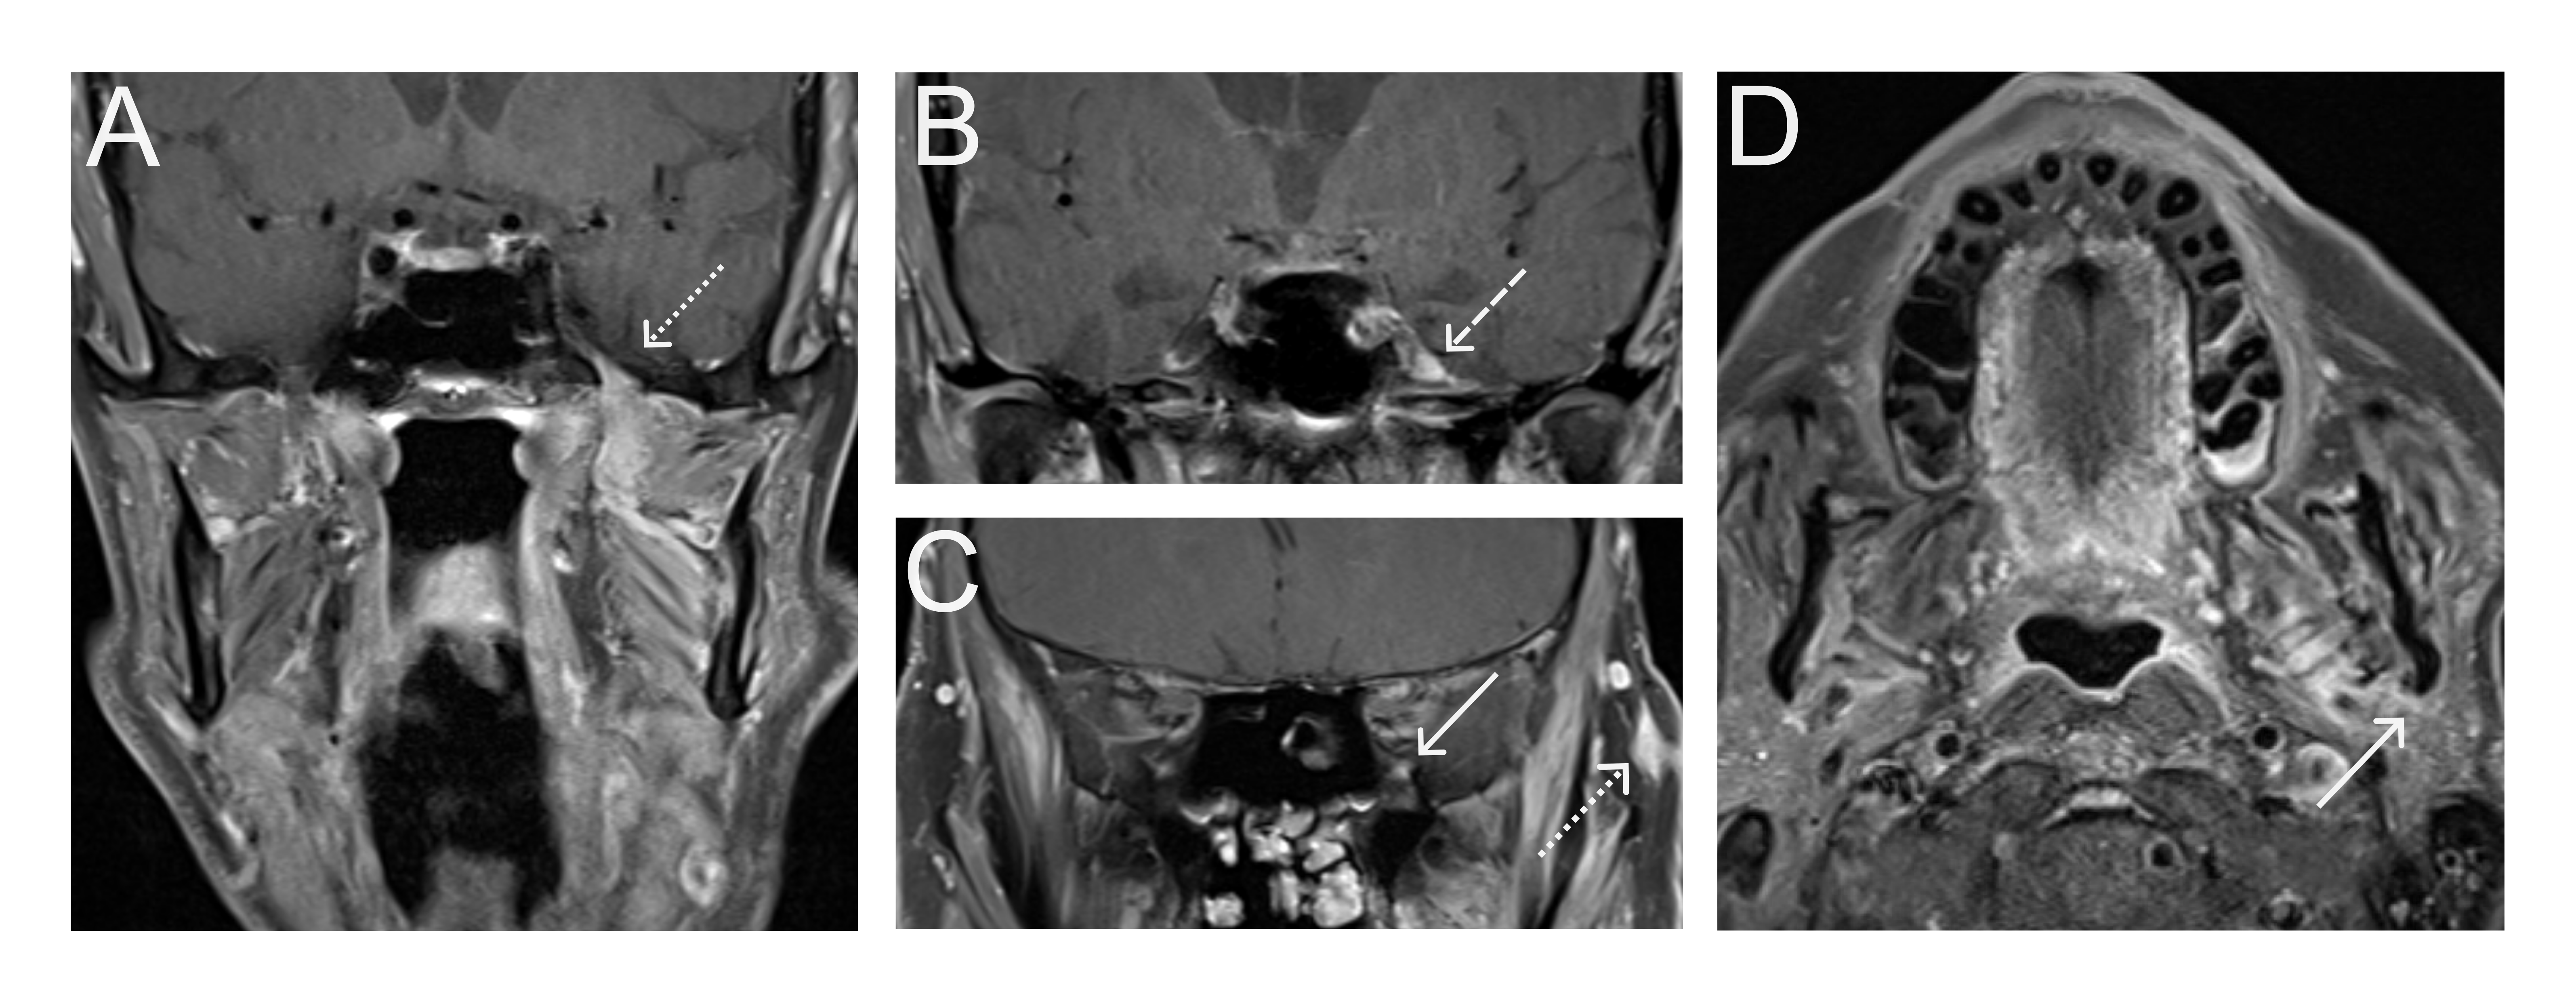

A 67-year old woman with chronic hypertension, hyperlipidemia and diabetes mellitus non-compliant to medication presented with a 10-day history of recurrent visual phenomena in the left visual field. She described stationery multi-coloured flashing lights which decreased in intensity, brightness and size after 3 minutes. She was alert and conscious during attacks. There was no limb jerking. Neurological examination was normal with no visual field defect. Capillary glucose was 28.1 mmol/L, Hba1c 9% and B-hydroxybutyrate < 0.1. She was treated with actrapid 8 units, glipizide 5 mg BD and empagliflozin 12.5 mg OM. Interictal electroencephalogram was normal with no epileptiform activity. Brain magnetic resonance imaging revealed restricted diffusion in the right occipital cortex with corresponding cortical thickening and increased FLAIR signal with subtle hypodensity on GRE sequence. Her visual symptoms improved dramatically with hydration and diabetic control. She was treated with a short course of keppra. One month later repeat MRI brain showed resolution of the DWI and FLAIR abnormalities.

Initial dwi

D